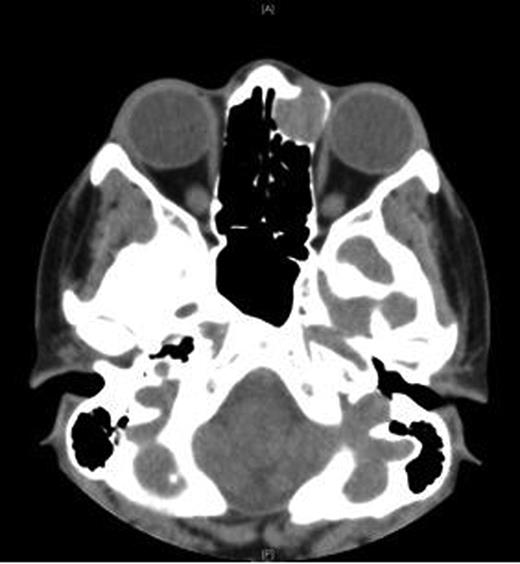

An MRI scan of the orbits showed a well-defined, thin-walled 22 × 16 mm cyst medial to the left orbit containing fatty/proteinaceous material, which was lying within and mildly expanding the left ethmoid air cells (Figs 1–3).

A CT scan of the paranasal sinuses and orbits revealed the cystic expansile 1.6 cm mass at the left medial canthus to be of soft tissue density. The lateral wall of the mass expanded outwards into the orbit (suggesting an anterior ethmoidal mucocele) rather than being pushed medially (which could have been indicative of a dacryocystocele) (Fig. 4).